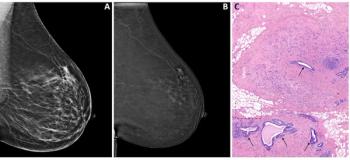

The feasibility of hub-and-spoke mammography, in which breast imaging studies are performed at satellite centers and read at a centralized reading station, has been confirmed through an evaluation of 30,000 cases and three years of clinical experience. The Columbia University study finds the transmission and interpretation of digital mammography exams to and from a remote location through commercially available high-speed cable Internet access is safe, reliable, and cost-effective.

Melton and colleagues reviewed more than 29,500 cases produced from two full-field digital mammography devices and read by a digitalcomputer-aided detection system at an offsite screening facility. Cases were sent to a mammography workstation in a primary diagnostic center usinga two-way DICOM protocol. They went through a virtual private network via cable Internet. Findings were presented at the 2008 American Roentgen Ray Society meeting.